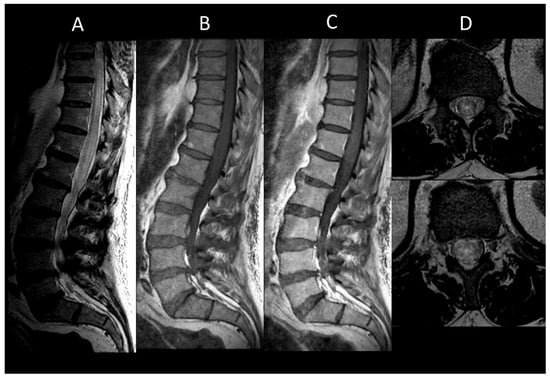

3.5. Metabolic and Toxic Myelopathies

Subacute Combined Degeneration of the Spinal Cord and Mimics

- Kumar, N. Metabolic and Toxic Myelopathies. Semin. Neurol. 2012, 32, 123–136. [Google Scholar] [CrossRef]

- Jaiser, S.R.; Winston, G.P. Copper Deficiency Myelopathy. J. Neurol. 2010, 257, 869–881. [Google Scholar] [CrossRef]

- Pinnix, C.C.; Chi, L.; Jabbour, E.J.; Milgrom, S.A.; Smith, G.L.; Daver, N.; Garg, N.; Cykowski, M.D.; Fuller, G.; Cachia, D.; et al. Dorsal Column Myelopathy after Intrathecal Chemotherapy for Leukemia. Am. J. Hematol. 2017, 92, 155–160. [Google Scholar] [CrossRef]